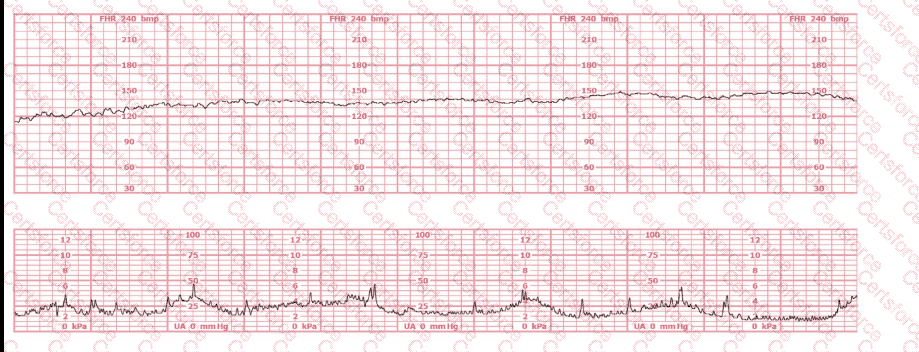

The baseline fetal heart rate in this tracing is:

Question # 2

155 beats per minute

Indeterminate

Tachycardia